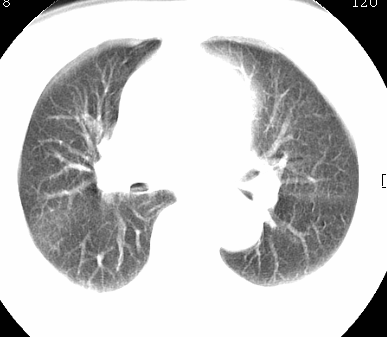

标题: CT26680:肺部右下肺静脉干结节的界定 [打印本页]

标题: CT26680:肺部右下肺静脉干结节的界定

考虑1、周围型肺癌,2肺静脉畸形,前者可能大,建议增强检查。

中心型肺癌,纤支镜可帮助明确。